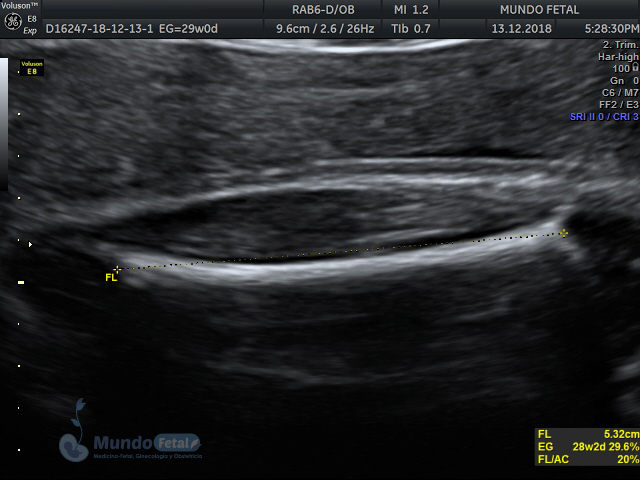

Mediante esta técnica ultrasonográfica, evaluamos en tiempo real al bebe y monitoreamos electrónicamente la frecuencia cardiaca fetal, vigilando los siguientes parámetros:

A cada parámetro se le asigna un puntaje basado en una escala del 0 al 10. Se ha propuesto que en estados fetales alterados por disminución del oxígeno se alteran los parámetros de manera que podemos predecir el estado fetal evaluando estos puntos.